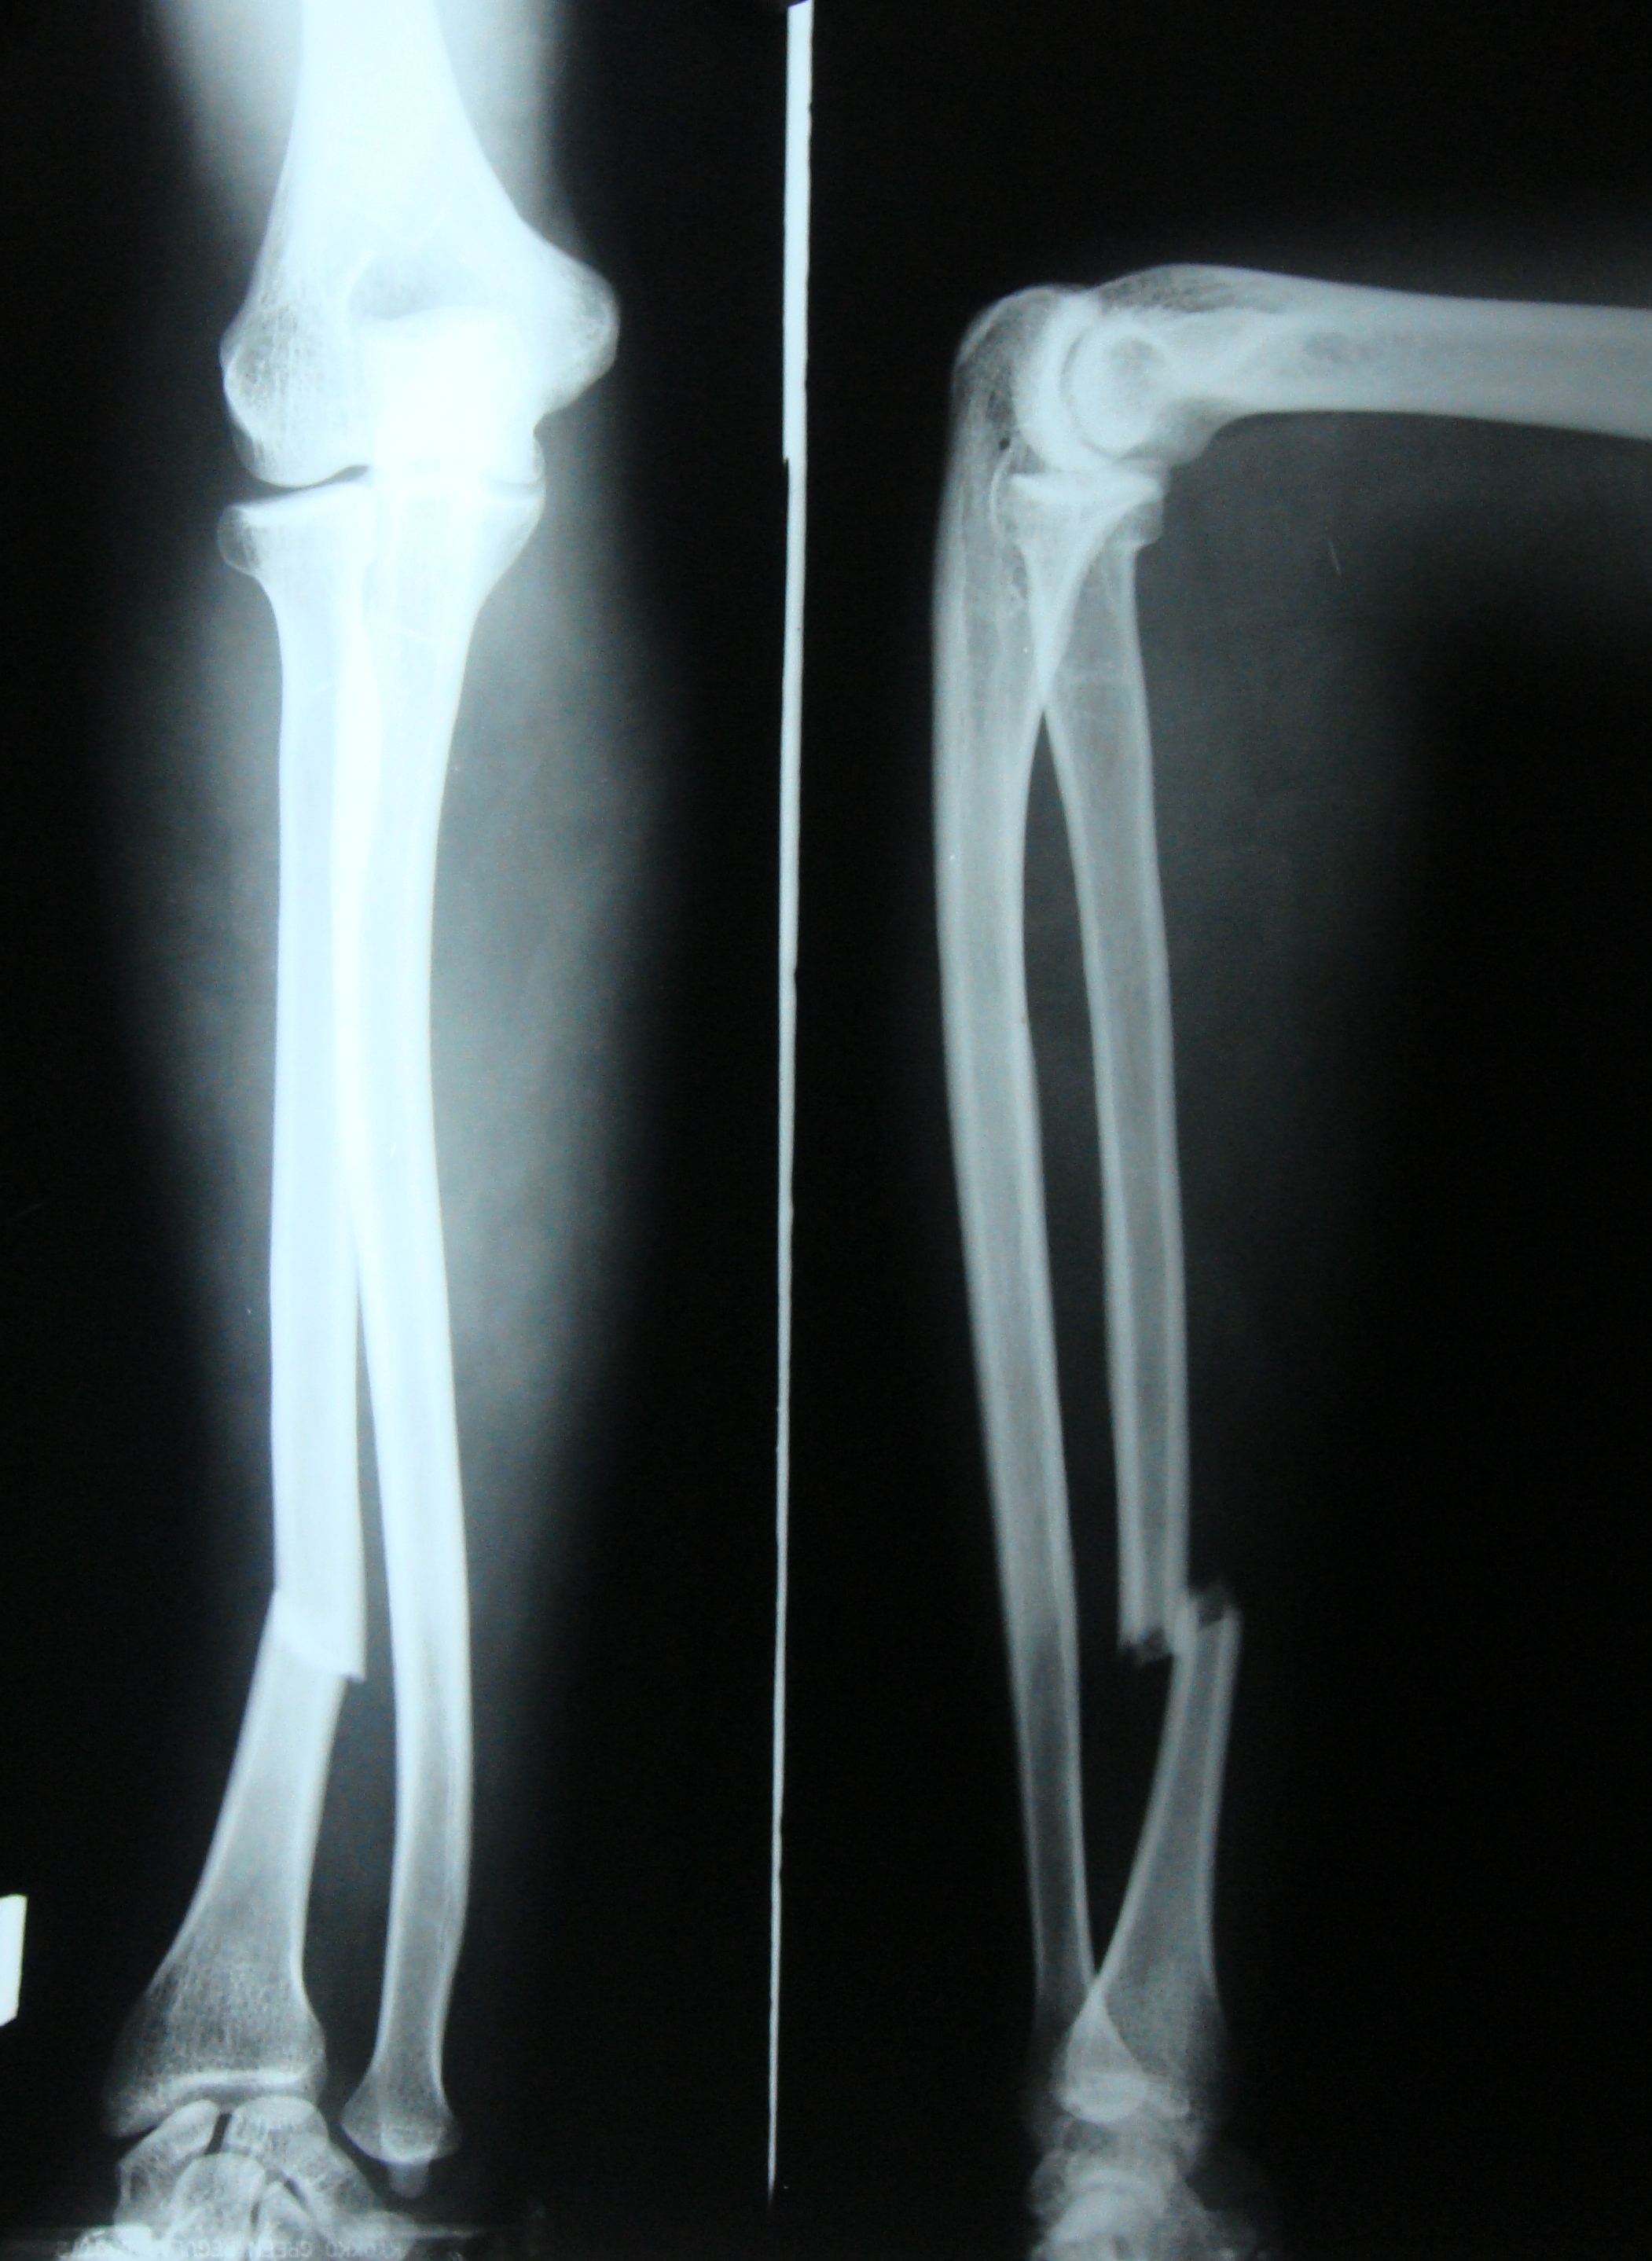

Fractures may be open, where the bone protrudes through the skin or closed, where the broken bone does not pierce the skin. Types of Forearm Fractures in Childrenįorearm bones may break in many ways. Thus, if a fracture is suspected in a child, it is necessary to seek immediate medical attention for proper alignment of the bones. The healing of fractures in children is quicker than that in adults. The growth plate, which is made of cartilage (flexible tissue) is present at the ends of the bones in children and helps in the determination of length and shape of the mature bone. Apart from this, the bones in children are prone to a unique injury known as a growth plate fracture. Forearm fractures can occur near the wrist, near the elbow or in the middle of the forearm. The radius (bone on the thumb side) and ulna (bone on the little-finger side) are the two bones of the forearm.